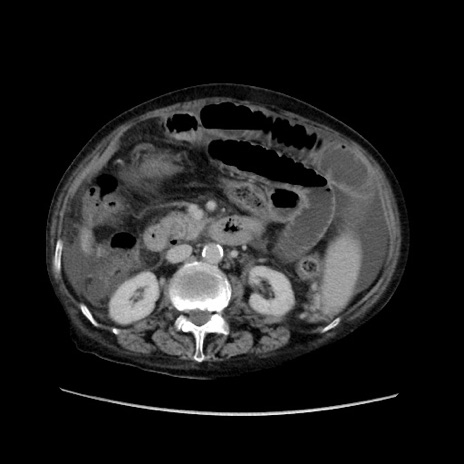

症例31(横断像)

【症例】80歳代 女性

【主訴】腹部膨満感

【現病歴】他院にて肝硬変にてフォロー中。1週間前から便秘、腹部膨満感、臍部腫瘤あり受診となる。

【既往歴】肝硬変

【身体所見】腹部膨隆あり、皮膚変化なし、疼痛なし。

【データ】WBC 4600、CRP 0.25